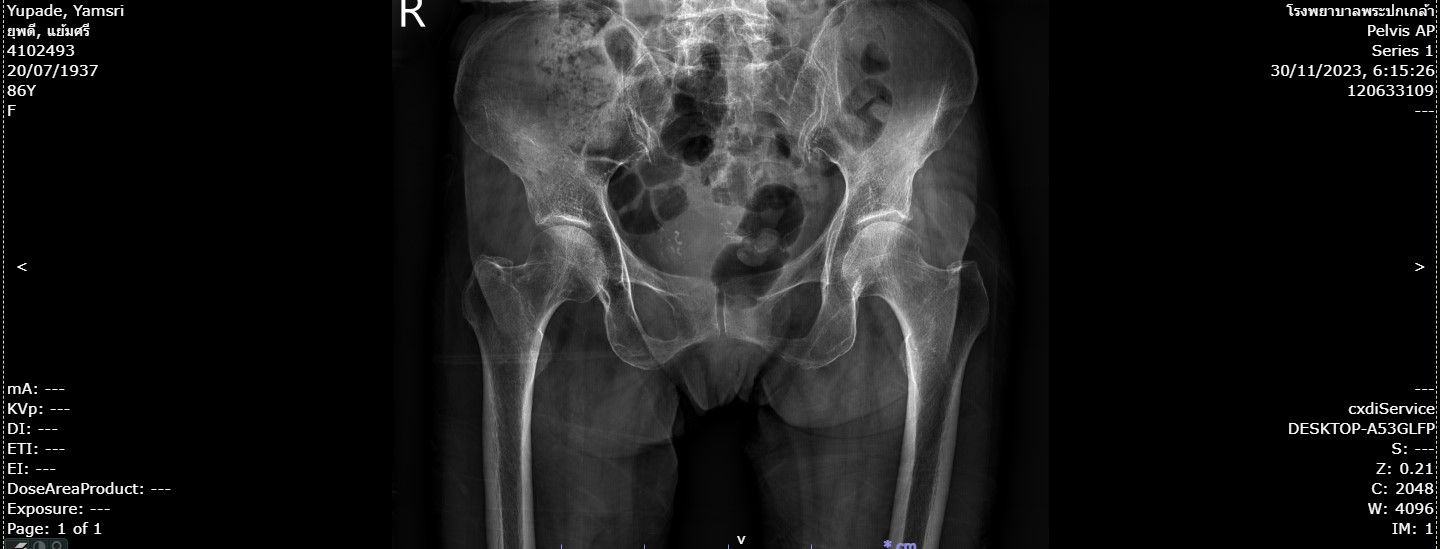

178ยุพดี.jpg                             17-Apr-2024 01:28              106092